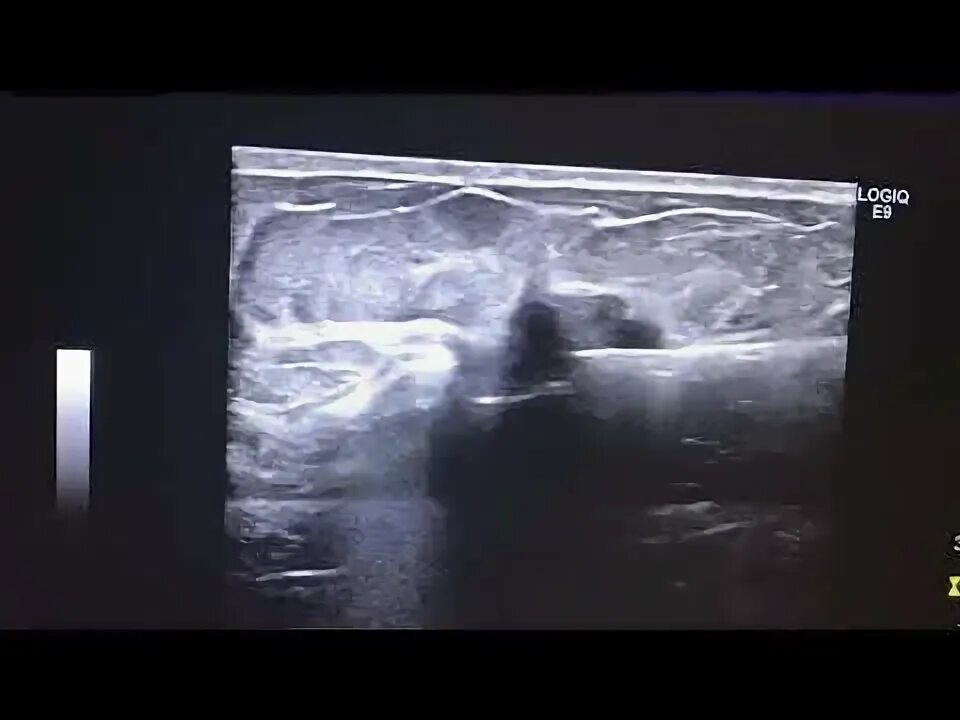

Вакуумное удаление фиброаденомы молочной